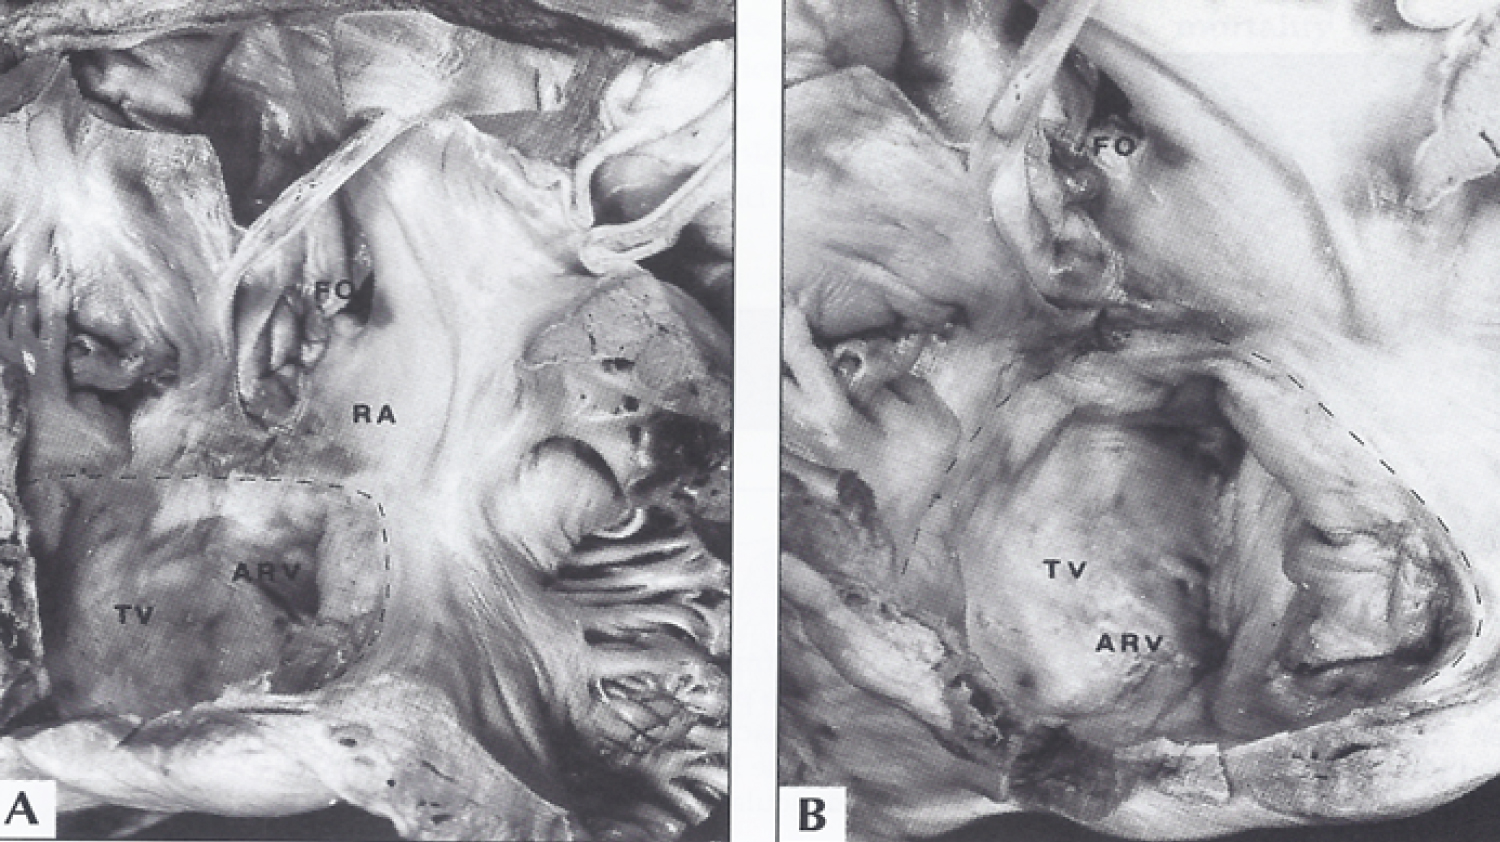

Figure 8: A) The interior of the right atrium and of the atrialized right ventricle (ARV) in a patient with tricuspid atresia with Ebstein's malformation are shown. B) This is a close-up of A. The interrupted line demarcates the true tricuspid valve annulus. The tricuspid valve (TV) leaflets are displaced downward (Ebstein's malformation) and fused, incorporating a part of the right ventricle into the right atrium (RA) [41].

FO: Fossa Ovalis. View Figure 8